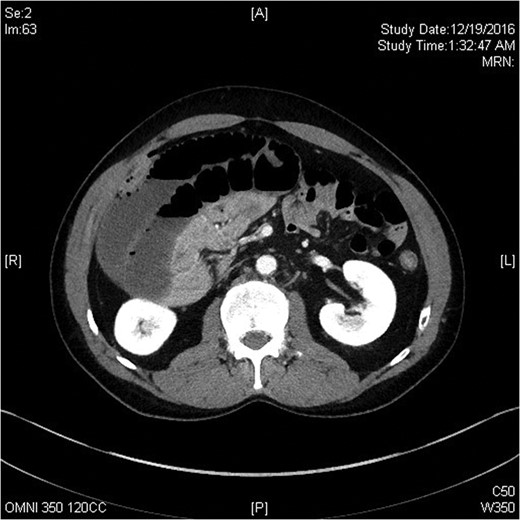

Computerized tomography scan of the abdomen in axial view demonstrating small bowel volvulus.